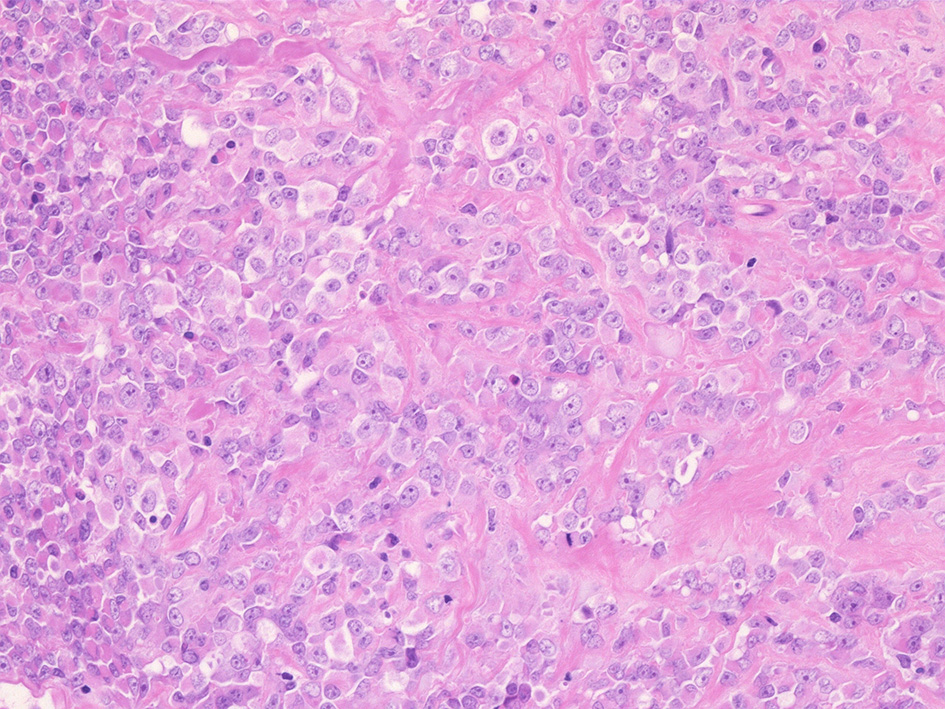

① rhabdoid cellsが密に増殖する組織像. 核は類円形vesicularで, 中心性の大型核小体を1個もつ. 細胞質は好酸性.

球状の封入体様にみえる構造が出現し, 核偏在や核を圧排し, 三日月/半月状の核がみられている. mitosisが散在. 形質細胞が少数混在して認められる.

② 少量の線維性組織を間質に類円形/多稜形のvesicularな核と好酸性, 淡明な細胞質をもつ類上皮様の中~大型の細胞が集簇, 増殖している.mitosisが多い. 辺縁にはrhabdoid cellsのchohesiveな増殖が認められる.

③ 間質の線維組織が多く, 硝子化やmyxomatous changeが認められる. 二核の大型巨細胞が散在している. 細胞は比較的一様なサイズ形態で, 多型は高度ではない印象.